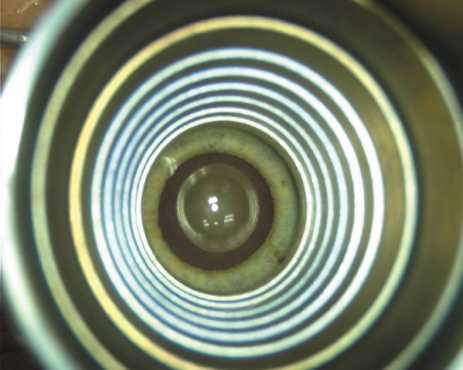

Proper centration of the incisions over the steep corneal meridian is of utmost importance. Increasing evidence supports the notion that significant cyclotorsion may occur when assuming a supine position.32 As previously noted, an axis deviation of only 15 degrees may result in a 50% reduction of surgical effect.5 For this reason, most surgeons advocate placing an orientation mark at the 12:00 or 6:00 limbus while the patient is in an upright position. This is particularly important when employing injection anesthesia wherein unpredictable ocular rotation may occur. An additional measure that may be employed to help center the relaxing incisions is to identify the steep meridian (plus cylinder axis) intraoperatively using some form of keratoscopy. The steep meridian over which the incisions are to be placed corresponds to the shorter axis of the reflected corneal mire. A simple handheld device such as the Maloney (Storz, Katena) or Nichamin (Mastel Precision) keratoscope works well, or a more robust and well-defined mire may be obtained through an elaborate microscope-mounted instrument such as the Mastel Ring of Light (Mastel Precision). Another common way in which the steep meridian is marked utilizes a Mendez Ring or similar degree gauge that is aligned with the previously placed limbal orientation mark, and the cylinder axis is then located on the 360-degree gauge.

Case 3 is a 48-year-old bilateral hyperope who presented for a refractive surgical consultation. The refraction in his left eye was found to be +3.25 +1.75 × 85. Keratometry was somewhat flat but confirmed WTR cylinder as did corneal topography. Based upon the patient's age, refraction, and somewhat shallow anterior chambers, the decision was made to proceed with a refractive lens exchange. The NAPA nomogram called for LRIs of 55 to 60 degrees with intraoperative pachymetry. Intraoperative keratoscopy confirmed the steep 85-degree meridian (Figs. 2029).

Fig. 20. Keratoscopy, after lifting of the speculum to relieve induced pressure and distortion of the corneal mires, confirms the steep axis of 85 degrees.